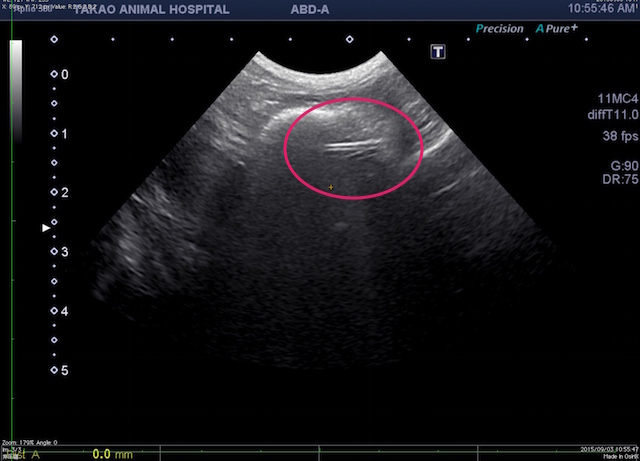

エコー検査でみてみると、胃内に人工物を疑わせるようなラインの異物を疑う所見がありました。

早速、内視鏡にて胃内を確認。すると、やはりありました。